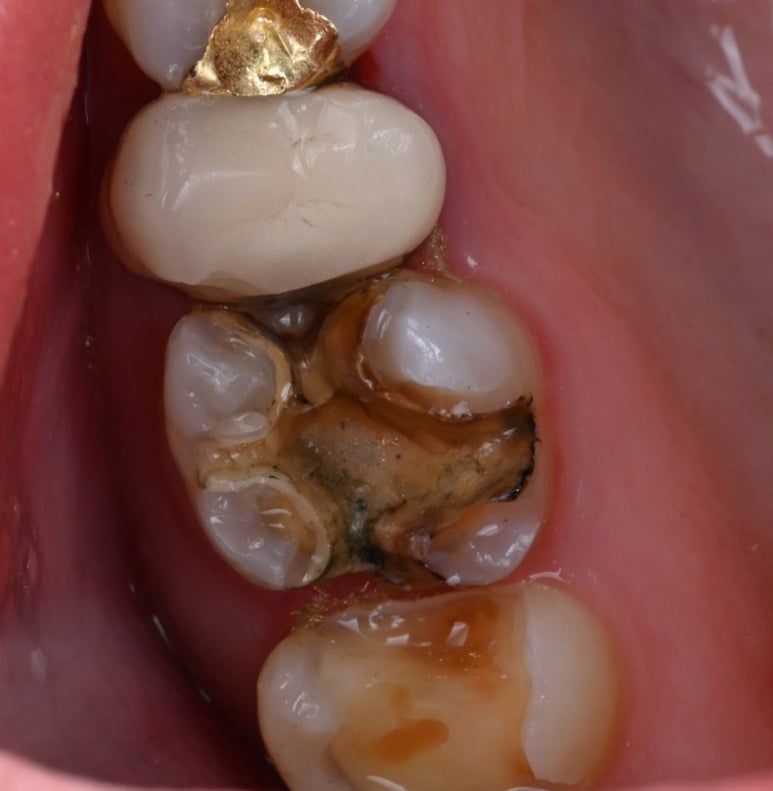

앞쪽 어금니는 인레이를 제거해 보니

충치 범위가 넓어, 치아의 씹는 면을

전체적으로 보호해 주는

'세라믹 오버레이(Overlay)'를 적용하기로

결정했습니다.

25.11.11 금인레이 제거 후 모습